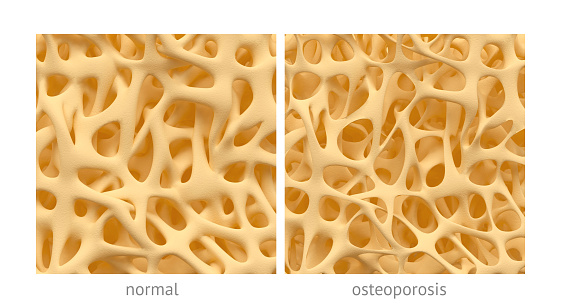

Psoriasis and general bone loss have been found to be linked and studies suggest it may help osteoporosis treatment research. Researchers from the Genes, Development and Disease Group found that psoriasis patients experience higher levels of bone loss as a result of the disease. Their findings, published in Science Translational Medicine, described the molecular communication ...click here to read more